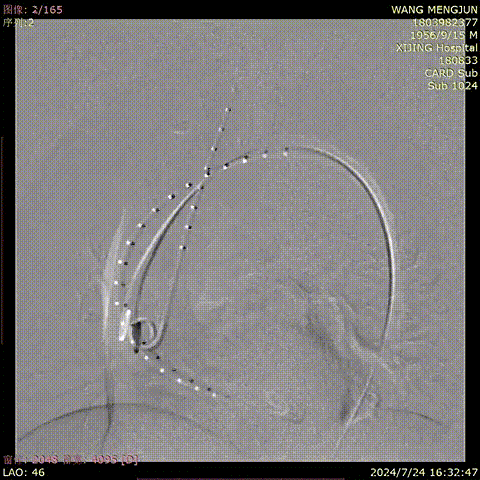

王某,男,67岁,“查体发现主动脉弓部动脉瘤7天”入院,主动脉CTA提示:主动脉弓部夹层动脉瘤。

术前CTA

术前造影

术后造影

手术用时 80 分钟